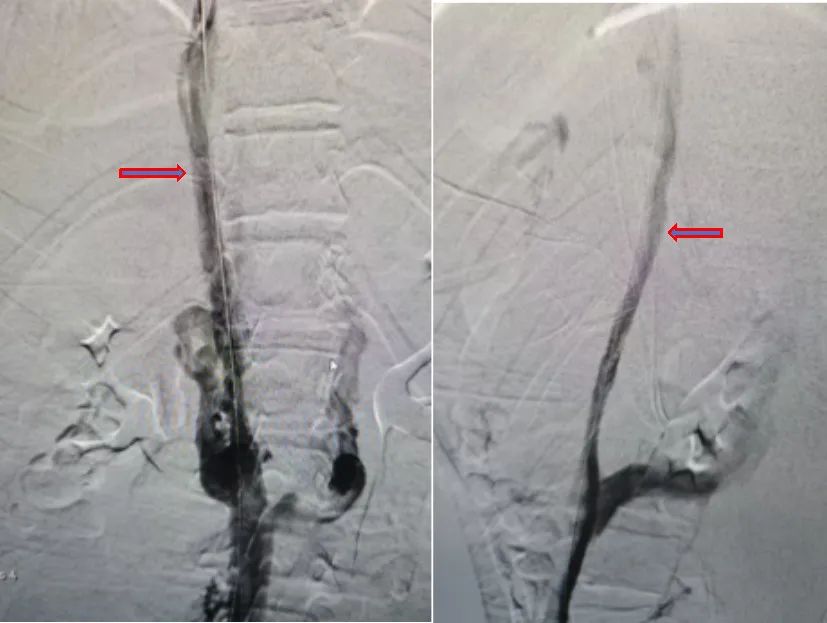

在制定了严谨的治疗方案后,于12月10日,为患儿进行了下腔静脉狭窄球囊扩张术。术中可见下腔静脉肾段至下腔静脉肝段未见下腔静脉显影,双侧可见侧支循环建立,经过血管再通,术后造影提示下腔静脉狭窄段缓解并再通,疾病得以缓解。患儿术后半月,未再出现腹痛,告别了两年来疾病对身体的折磨,这个正值花季的少女终于迎来了自己健康的青春时光。

球囊扩张术后,正侧位造影,可见下腔静脉再通